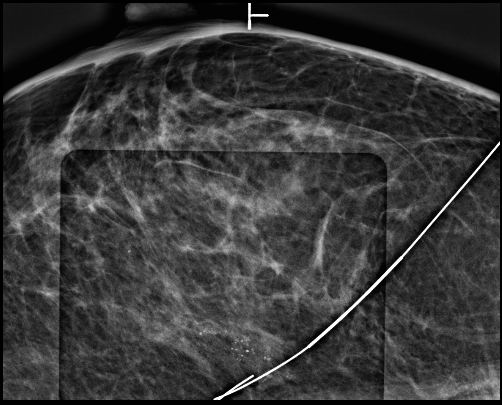

钙化灶在乳房中通常微小且无法直接触摸到。如何确保外科医生在手术中能精准找到这些“隐形目标”?这就是钼靶引导无可替代的作用:

精准定位: 在钼靶机实时透视下,将一根纤细的定位导丝准确穿刺植入到钙化灶的中心或紧邻区域。

路径规划: 医生会根据钙化位置和导丝入路,设计最合适、创伤相对小的手术切口。

标本验证: 手术切除包含导丝尖端(即目标钙化区域)的组织块后,需立即进行标本钼靶摄片。这是关键质量控制步骤